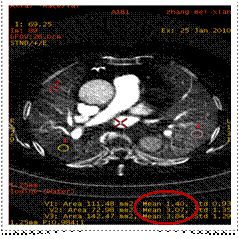

ROI 1(低灌注区): 碘的物质浓度1.40mg/ml

ROI 2(同侧肺对照区)碘的物质浓度3.07mg/ml

ROI 3(对侧肺同区域)碘物质浓度 3.84mg/ml

宝石能谱CT开创了CT定量分析的新时代。